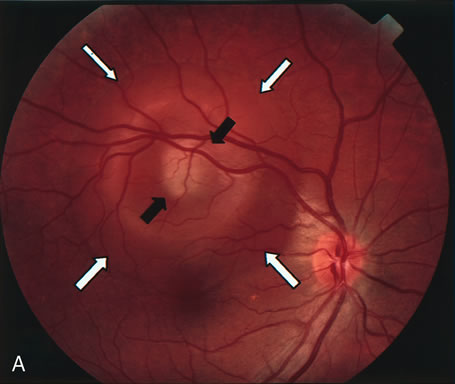

Clinically discernible peripheral dependent bullous neurosensory detachments have been described in patients with chronic CSC.85–92 Yannuzzi and co-workers first characterized the presence of RPE atrophic tracts extending inferiorly in the fundus periphery secondary to antecedent retinal detachment in patients with CSC.85 Presumably, there is a particularly severe and/or longstanding leakage of fluid from an RPE defect in the subretinal space at the posterior pole. The subretinal fluid gravitates inferiorly to form a dependent neurosensory detachment in a “flask,” “teardrop,” “dumbbell,” or “hourglass” pattern (Fig. 31). Sometimes the tract of subretinal fluid connecting the macular detachment with the bullous neurosensory detachment in the inferior hemisphere is so shallow that it is very difficult to appreciate. The RPE under the chronic retinal detachment experiences atrophic changes that appear as atrophic RPE tracts connecting the posterior pole with the dependent retinal detachment. The retina itself develops secondary manifestations including pigment migration, capillary dilatation (telangiectasia) proximally and capillary nonperfusion (ischemia) distally to the area of detached retina (see Fig. 31). The changes in the RPE consist of both RPE atrophy and pigment clumping in the form of perivascular deposits or bone spicules, a condition described by Gass as a “pseudoretinitis pigmentosa–like atypical CSC presentation.”87

Fig. 31. A 47-year-old woman with an18-year history of central serous chorioretinopathy in both eyes. A. Color photograph composite of the left eye shows bullous dependant detachment of the neurosensory retina inferiorly. B. Fluorescein angiogram composite reveals diffuse decompensation of the retinal pigment epithelium, multiple scattered pigment epithelium detachments 9PEDs), and obliteration of the retinal capillaries in the region of the detachments. Note the presence of early neovascularization at the junction between perfused and non-perfused retina. C. Clinical photograph of the left eye shows PED superior to the optic disc partially surrounded by fibrin deposits. D. Fluorescein angiography confirms the presence of active leakage from the serous PED. E, Color photograph composite of the same eye 2 months after laser treatment of the site of leakage reveals partial resolution of the detachment and lipid precipitation. F. Clinical photograph composite 16 months after the laser treatment in the area of the leakage shows complete resolution of the detachment and partial reperfusion of the inferior retina.